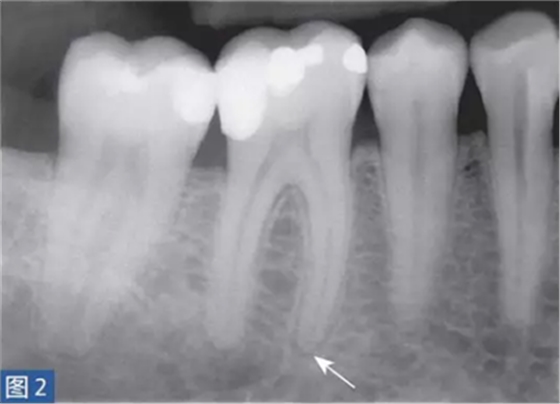

從牙髓炎過渡到根尖周炎(圖2 和3)的發(fā)生速度非常快,牙齒表現(xiàn)可能從正常到對(duì)冷、熱和電刺激的反應(yīng)越來越強(qiáng)。當(dāng)牙髓已經(jīng)完全壞死時(shí),通常會(huì)顯示對(duì)牙髓電活力測(cè)試無反應(yīng)。牙齒可能會(huì)有伸長感,用手指或口鏡柄施加壓力或者振動(dòng)牙齒會(huì)觸發(fā)非常嚴(yán)重的疼痛。放射學(xué)檢查可能存在透射區(qū)及根周膜間隙增寬,通常硬骨板和牙周韌帶沒有病理學(xué)特征。

圖2: 46 牙齒SAP。術(shù)前X 線片,該牙齒在其他醫(yī)生處已行齲齒治療?;颊咴V牙齒有明顯的咬合痛以及強(qiáng)烈的冷熱刺激敏感癥狀。放射學(xué)檢查,近中根根周膜間隙略增寬。

圖3: 46 牙齒SAP。根管治療6個(gè)月后。